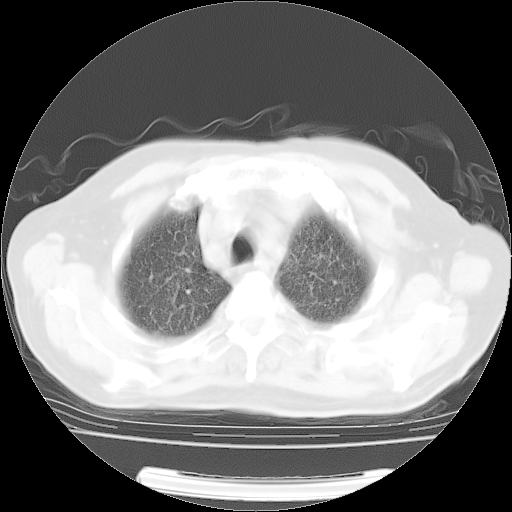

肺部CT平扫未见异常。